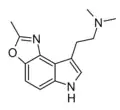

| 4,5-Methylbenzodioxole-DMT (P-131) | artificial | 4,5-(OC(CH3)=N) | CH3 | CH3 | N,N-dimethyl-2-(2-methyl-6H-[1,3]oxazolo[4,5-e]indol-8-yl)ethan-1-amine | |